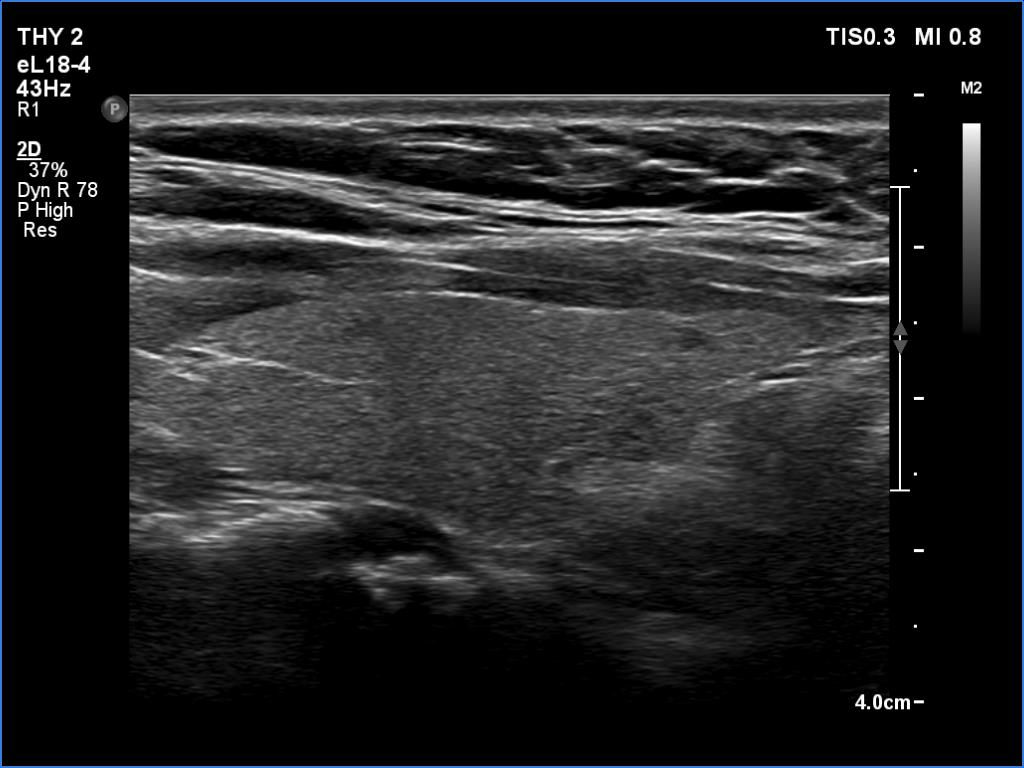

Thyroid cancers - case 842 (ultrasonographic picture 2)

Right lobe, longitudinal scan. The tiny hypoechoic areas have no importance